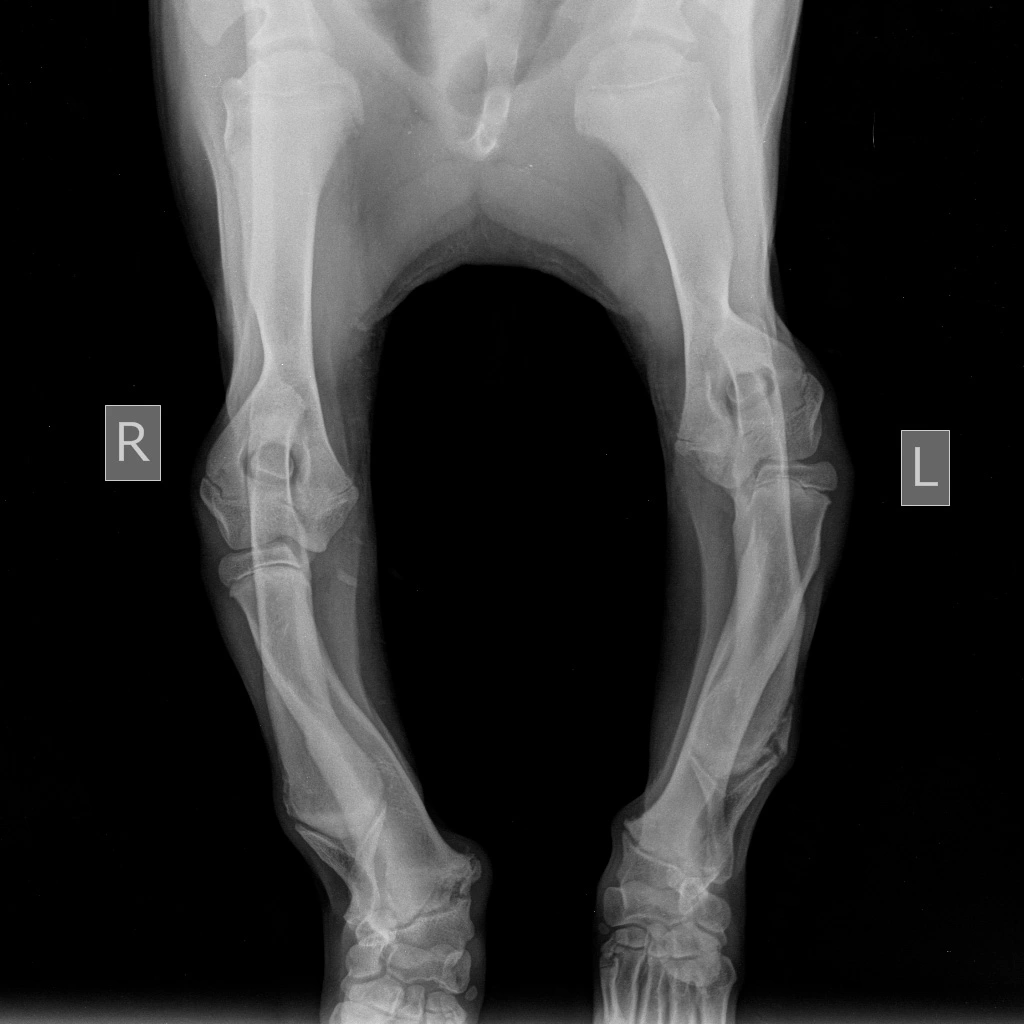

Как проводится лечение укороченной локтевой кости?

Консервативное лечение включает в себя «клеточное содержание», нормализацию кальцие-фосфорного обмена по средствам нормализации рациона и контроль боли. Однако оно редко дает хороший результат.

Хорошо зарекомендовало себя хирургическое лечение — дистальная остеотомия локтевой кости. Данная операция снимает эффект «натянутой тетивы» с локтевой кости, при этом лучевая кость продолжает расти и начинает постепенно выпрямляться за счет продолжающегося роста. Данную операцию необходимо проводить в возрасте 4-7 месяцев т.к. зона роста лучевой кости еще не закрыта.

Если в 4-5-месячном возрасте была проведена дистальная остеотомия локтевой кости и она в течение 1-1,5 месяцев не приводит к видимым улучшениям, то в кратчайшие сроки применяют методику блокировки медиального участка дистальной ростковой зоны.

У мелких и хондродистрофичных пород собак хромота развивается позднее, примерно в 6-10 месяцев и связана она в основном с подвывихом локтевого сустава. У таких пород, особенно при наличии хромоты и отсутствии видимой деформации конечности, бывает достаточно проведение только проксимальной динамической остеотомии локтевой кости, для корректировки подвывиха.

Если данные виды хирургического лечения не оказывают достаточно хорошего эффекта, т.е. у животного наблюдается хромота и присутствует визуальные различия между передними конечностями, то прибегают к такой хирургической методике как корректирующая остеотомия лучевой кости. Но данная методика может быть использована только после окончания роста костей в длину (10-12 мес.) При данной методике разрезают (метод открытого клина) либо вырезают участок лучевой кости (метод закрытого клина) и место остеотомии фиксируют накостной пластиной или внешним фиксатором. Нередко при этой операции прибегают и к артродезу запястного сустава, в случае позднего обращения владельцев животного в клинику, т.к. из-за сильного давления на запястный сустав, в нем развиваются необратимые дегенеративные изменения.